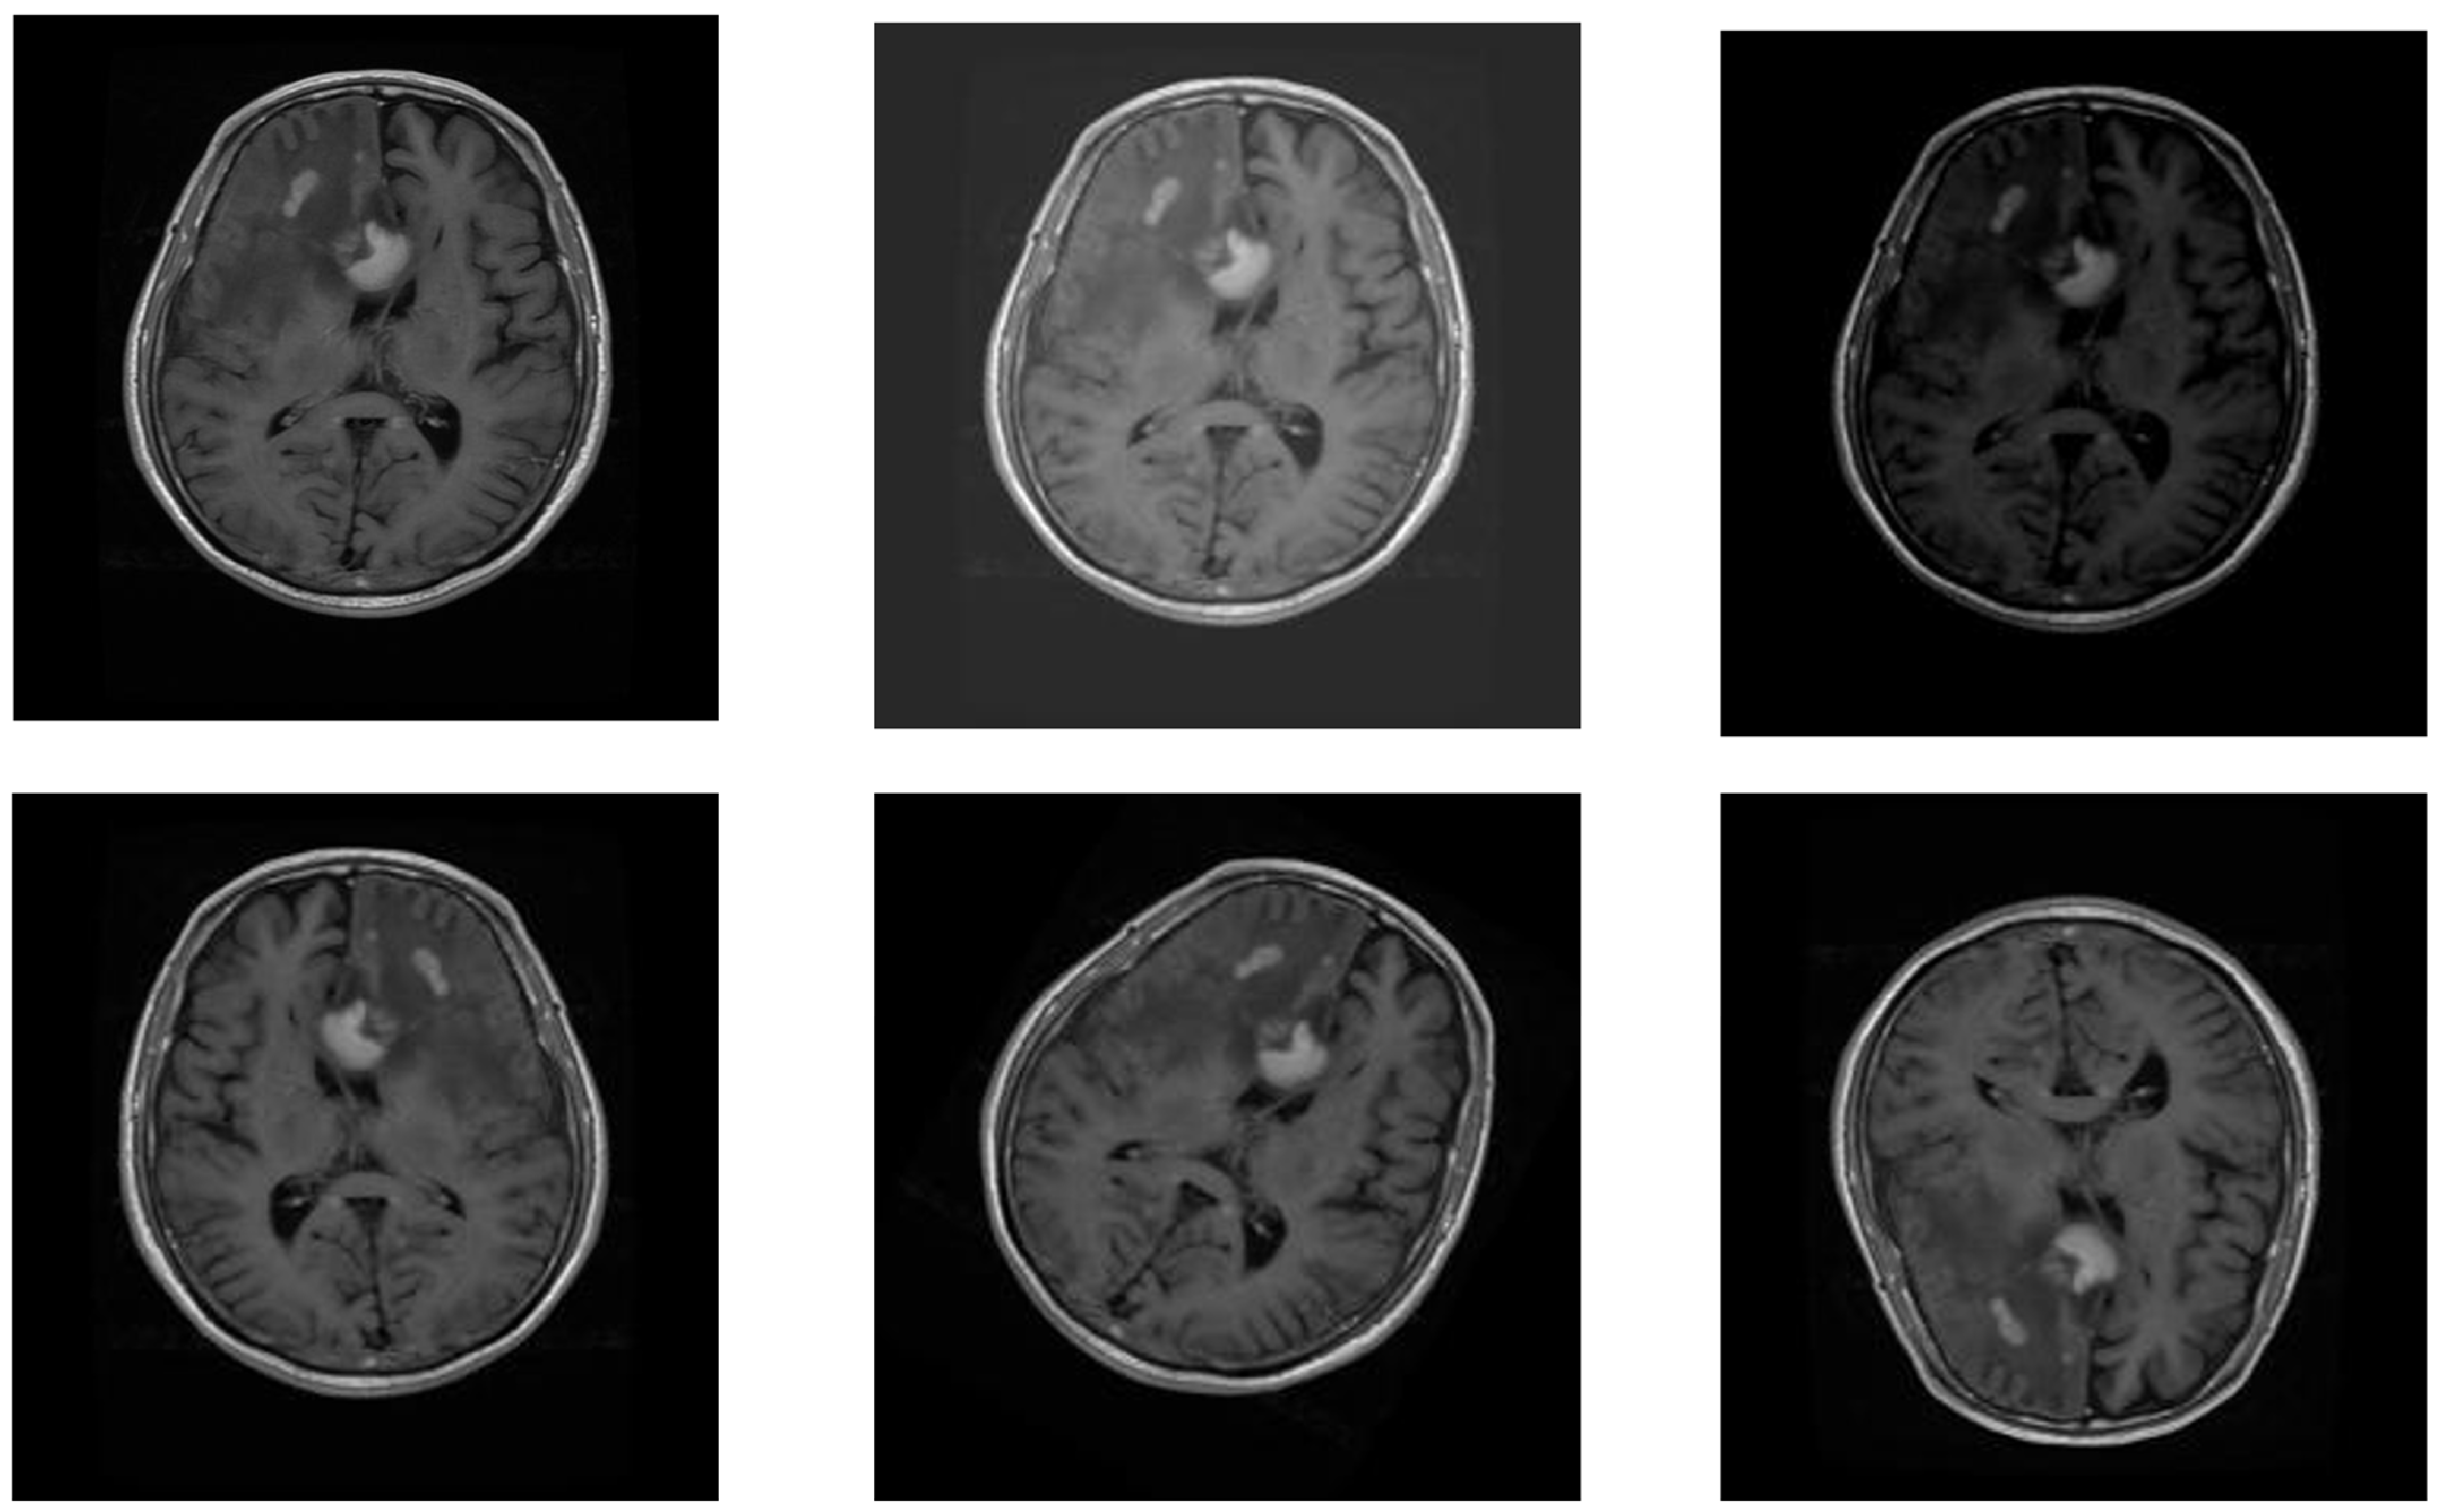

2.1.3. MRI Brain Scans

| Brain tumors | MRI Brain scans | 7019 | 4 | 300 × 300 |

| 7019 | 2 | 300 × 300 |

3.2.4. MRI Brain Scan Tumor Classification Model